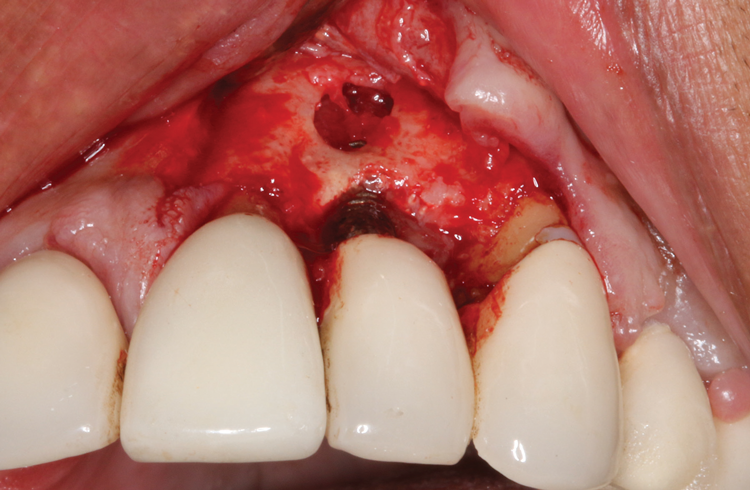

(3.) An envelope reflection was made with no vertical incisions, exposing the entire bony defect affecting the apical portion of the stable implant.

Figure 3

Following infiltration of the facial attached gingiva and palatal area with articaine hydrochloride 4% and epinephrine 1:100,000 (Septocaine®, Septodont [alternatively: Articadent®, Dentsply Sirona; Orabloc®, Pierrel]), an envelope releasing incision was made extending one full tooth over. To prevent trauma to the mucosal tissue, vertical incisions were not made (Figure 3). Incising the mucosa results in the release of prostaglandins and histamine, which increases postoperative discomfort. For this patient, staying in attached gingiva provided excellent control of the flap and allowed clear access to the apical lesion.